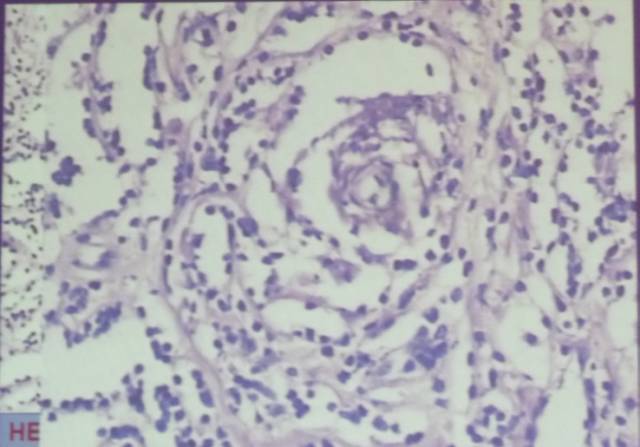

HE染色示:过度型脑膜瘤(同时含有上皮型脑膜瘤和纤维性脑膜瘤的病理特点),可见椭圆形及细长形肿瘤细胞,细胞边界不清,胶质纤维较少。